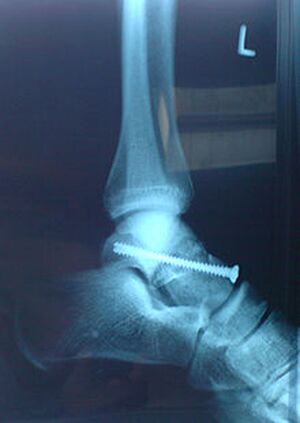

mit einer Schraube "repariertes" Sprunggelenk - Christian Kazur commons.wikimedia.org, CC BY 3.0

Das sind häufige Verletzungen im Sport.

Im Fußball können Zerreißungen der Außenbänder vor allem nach einem Tritt des Gegners gegen den Knöchel oder durch Umknicken bei der Landung nach einem Kopfball auftreten. Dabei überschreitet das ungeschützte Gelenk die Kippgrenze, der Muskel reagiert nicht schnell genug. Besonders ein übermüdeter und ungenügend aufgewärmter Muskel ist aufgrund seines herabgesetzten Reaktionsvermögens besonders gefährdet.

Bei Außenbandrissen im Bereich des Sprunggelenkes wird immer öfter ohne Operation behandelt. Nach Verschwinden der Schwellung erhält der Betroffene eine Plastikschiene, mit welcher der Fuß im Sportschuh nahezu wieder normal belastet werden kann. Bis zur völligen Ausheilung vergehen einige Wochen. Der Heilungsprozess kann durch Bewegungs- und Dehnübungen, sowie durch gezielte Elektrotherapie wesentlich unterstützt werden.

Bei Komplettabrissen und in speziellen Fällen ist meist eine Operation notwendig.